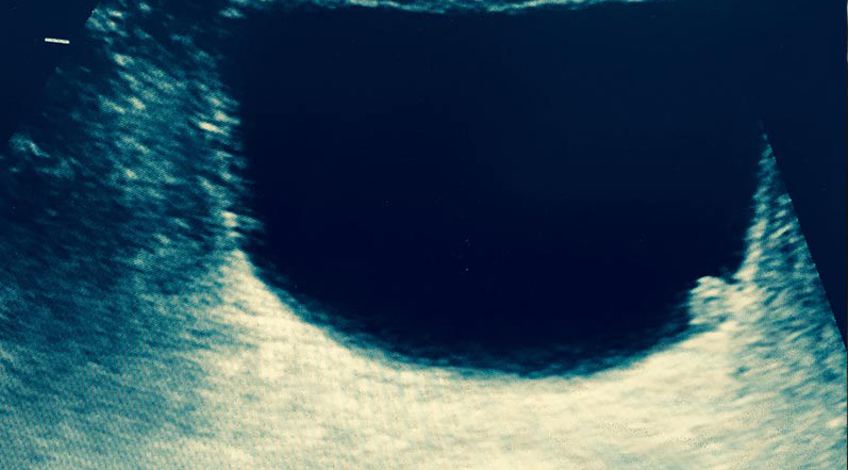

Ecotomografía Vesical

La ecografía vesical o de vejiga se realiza habitualmente con una sonda de baja frecuencia. Esta sonda se coloca en el bajo vientre y se va moviendo lentamente para explorar las distintas zonas de la vejiga y así poder detectar enfermedades y procesos que afectan a este órgano muscular.